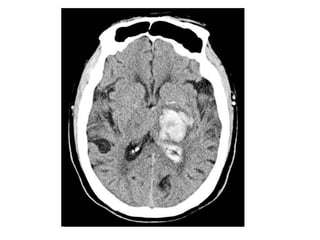

CT and T2W-gradient echo image of a hemorrhagic infarction

limited to the territory of the lateral lenticulostriate arteries